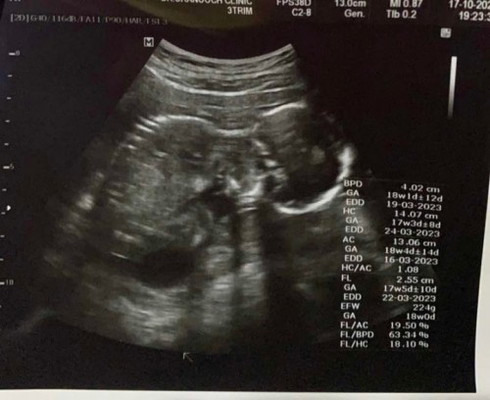

น้องไม่ยอมให้ดูเพศเลย แม่ตั้งหน้าตั้งตารอ ตื่นเต้นทุกครั้งเลย🥹💕🥰 18w1d